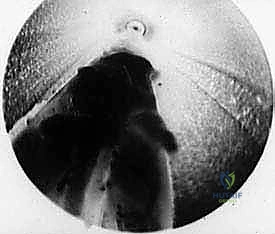

3. إدخال الكانيولا والمنظار:

يتم إدخال أداة مجوفة دقيقة (Cannula) عبر الشق الصغير، وتوجيهها بحذر شديد تحت الجلد وفوق الرباط المستعرض (TIML). بعد ذلك، يتم إدخال كاميرا المنظار (Endoscope) الدقيقة (عادة بقطر 2.7 ملم أو 4 ملم) عبر الكانيولا.

4. الرؤية المكبرة وتحديد الرباط:

تُعرض الصورة المكبرة بدقة 4K على شاشة أمام الجراح. يقوم الدكتور هطيف بتنظيف الأنسجة الدهنية الدقيقة برفق باستخدام أدوات متخصصة حتى يظهر الرباط المستعرض (TIML) بوضوح تام، وتظهر أليافه العرضية المميزة.

5. تحرير الرباط وتخفيف الضغط (The Release):

هذه هي الخطوة الأكثر دقة. باستخدام سكين جراحي دقيق مخصص للمناظير (Hook knife أو سكين رجعي)، يتم إدخاله تحت أو فوق الرباط. وبحركة دقيقة ومحسوبة، يقوم الدكتور هطيف بقطع الرباط المستعرض بالكامل من النهاية القريبة إلى النهاية البعيدة.

6. تأكيد التحرير:

بمجرد قطع الرباط، تتسع المسافة بين رؤوس الأمشاط فوراً. يقوم الدكتور هطيف بفحص المنطقة بالمنظار للتأكد من القطع الكامل للرباط، والتأكد من أن العصب تحرر تماماً من الضغط، مع التأكد من سلامة الأوعية الدموية المجاورة.